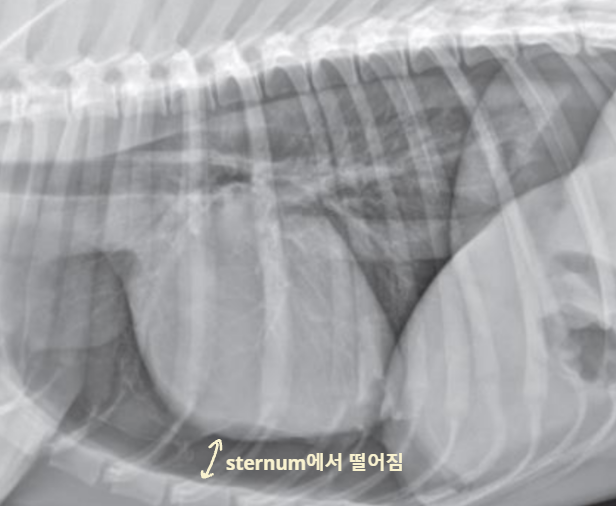

Hiatal hernia (위 허탈) : 위가 흉강으로 빠짐

Radiographic signs

interlobar fissure 두껍게 관찰되고,

흉벽이 떨어져 나간 것처럼 보임

- Interlobar fissure widening

- Lung retraction

- Pleural wall thickening

- Scallop sign

- Cardiac effacement

- Blunt angle

- Retraction of pleural surface

- Collapsed lung (→ opacity 증가)